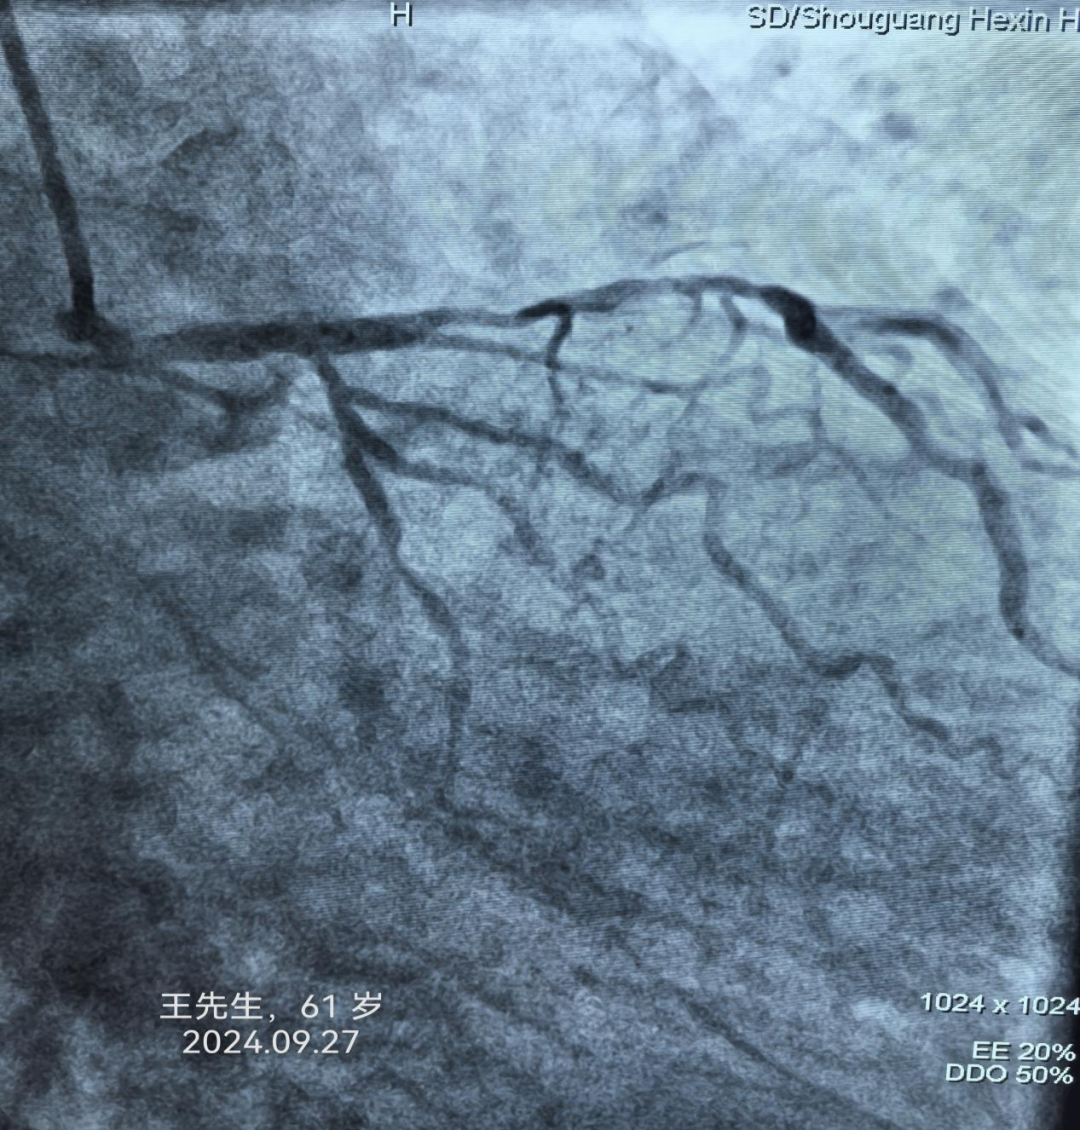

冠心病患者是猝死的高危人群。冠心病是中老年人最常见而且危害最大的心脏病之一,但随着生活节奏的加快和压力的增加,年轻人发病率也呈现增高的趋势。患者轻者可能无明显症状,但严重者可能会因此丧命。及时了解冠心病的早期症状对于早期发现和早期治疗有很大的帮助。